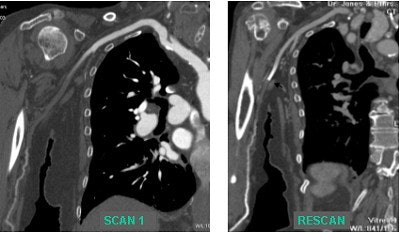

The capability of 16-slice CTA to rescan rapidly enables a second exam to better visualize extremity arterial occlusions, he reported. Improved tibial artery visualization provides very useful presurgical information for potential graft planning.

Clinical cases illustrate the advantages of 16-slice vs. 4-slice and 8-slice imaging. Evaluation using 16-slice imaging enabled vessel visualization over a distance of 1,800 mm, compared with 1,500 mm for 4-slice scanners. This was particularly relevant in the case of a tall man with coexisting carotid and iliac arterial disease. Images courtesy of Dr. Ruben Sebben.